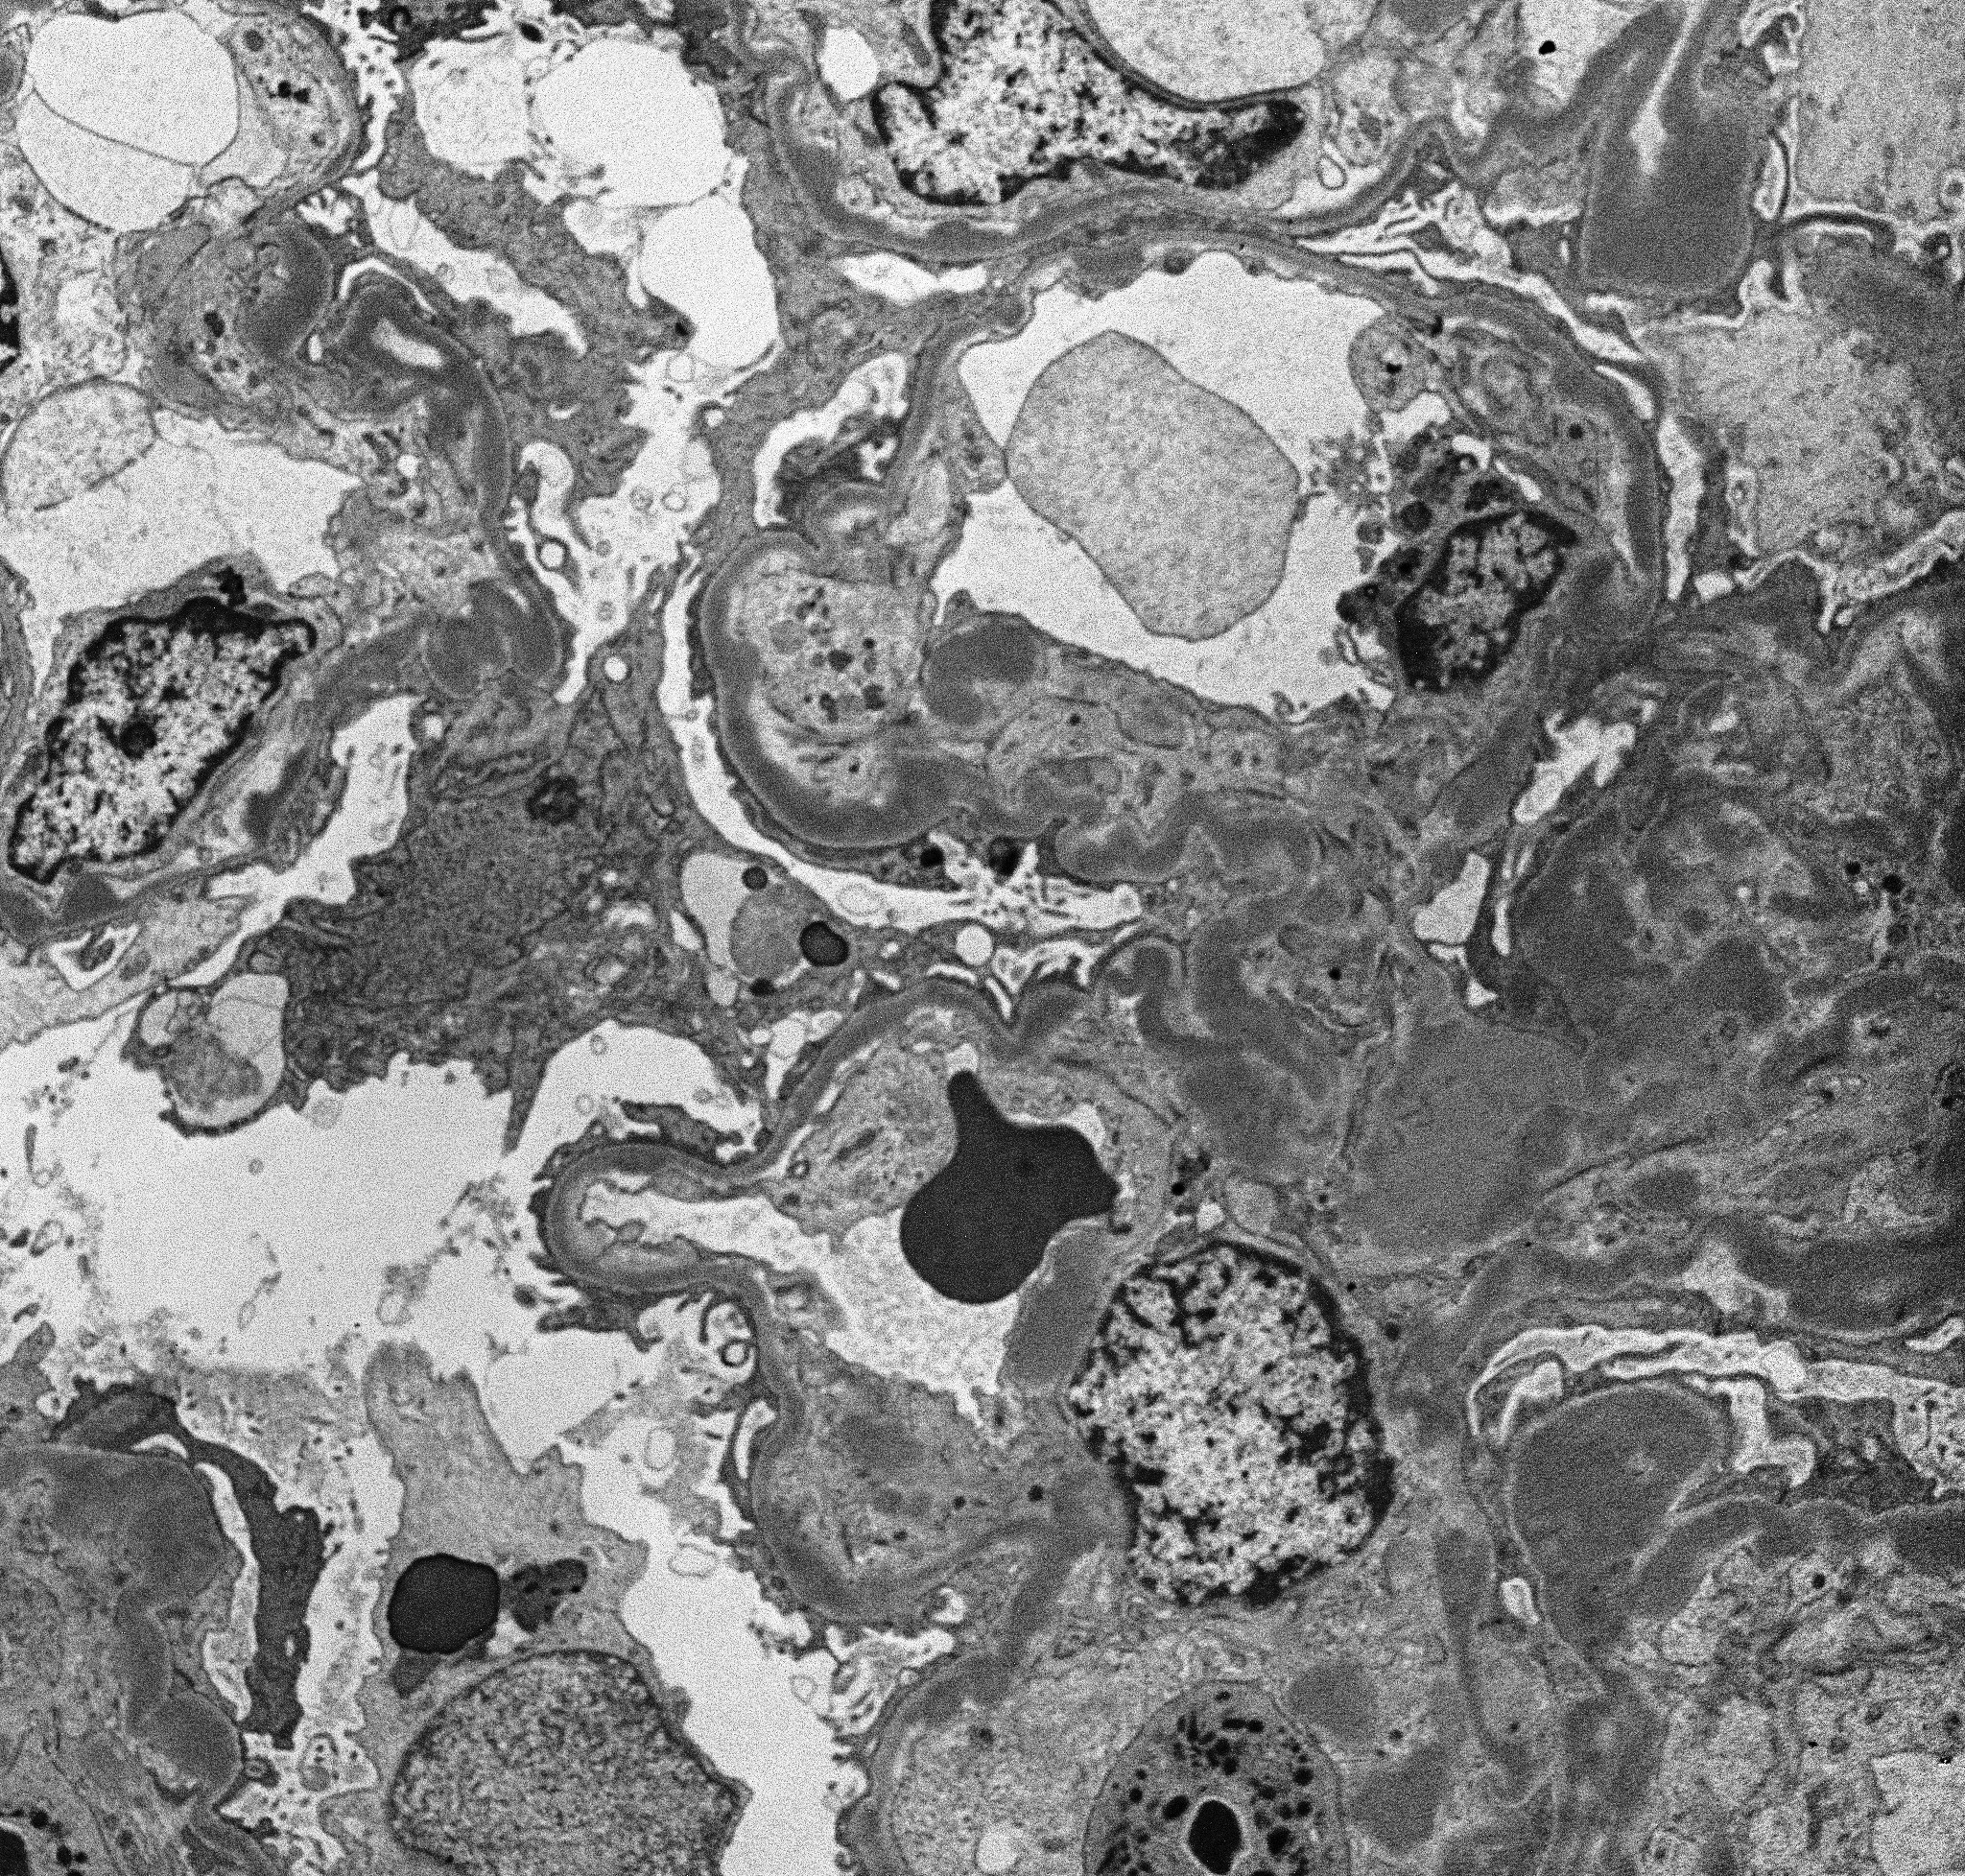

DDD, previously known as membranoproliferative glomerulonephritis (MPGN) type II, is now considered a subtype of C3 glomerulopathy, as MPGN pattern of glomerular injury, characterized by diffuse splitting of the glomerular basement membranes and mesangial hypercellularity with or without endocapillary hypercellularity (Fig A & B), is identified only in one third of the patients with DDD and is therefore misleading. The defining feature of DDD is ultrastructural finding of continuous, ribbon like, predominantly intramembranous, segmental subendothelial and mesangial globular intensely electron-dense deposits (fig: 4), from where the disease derives its name. These deposits show strong staining for C3 with absent or minimal staining for immunoglobulins and C1q, by immunofluorescence (Fig: 3).